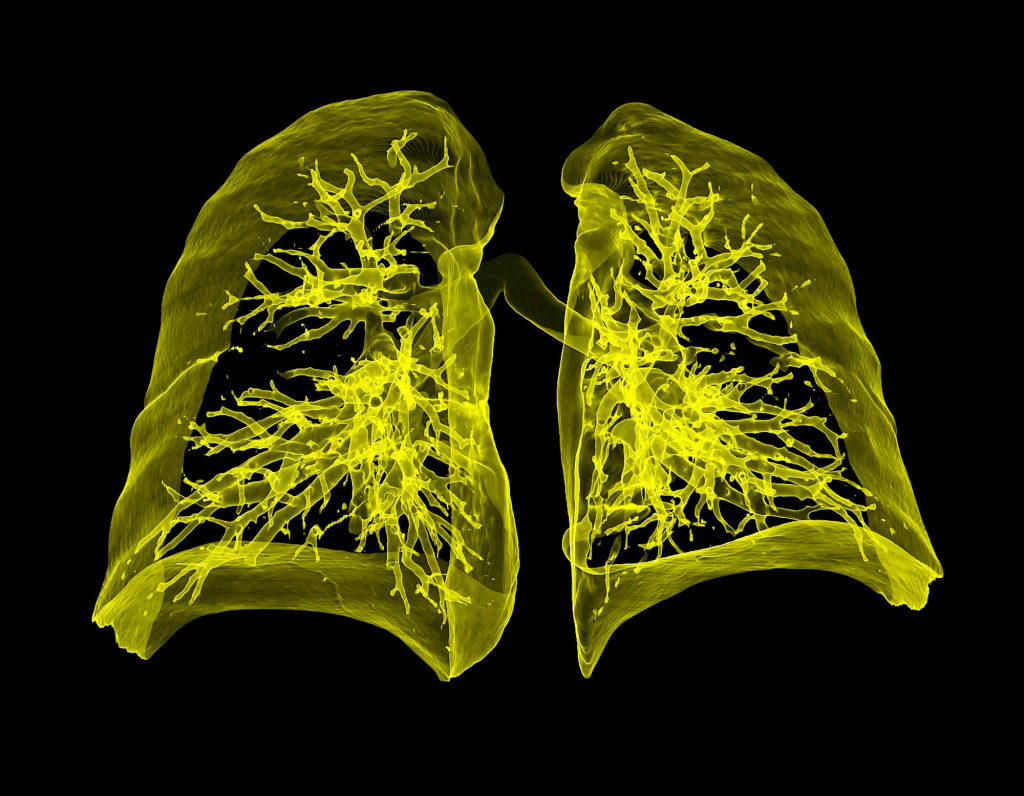

My favourite image is a 3D CT scan of lung airways.

It was one of my first images using a completely redesigned tissue density colour table. Green is the most dense tissue (bone) and purple is the least dense tissue (lung).

Combining these colours resulted in an extremely bright artistic image.